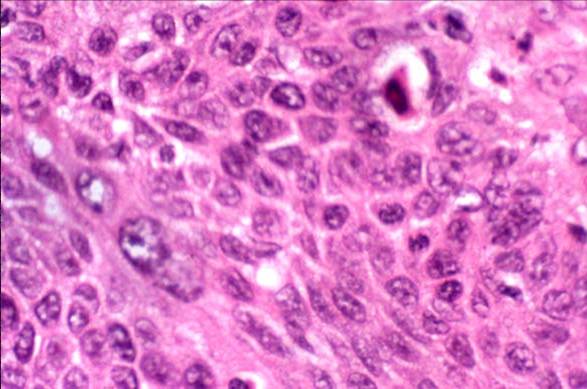

cervix